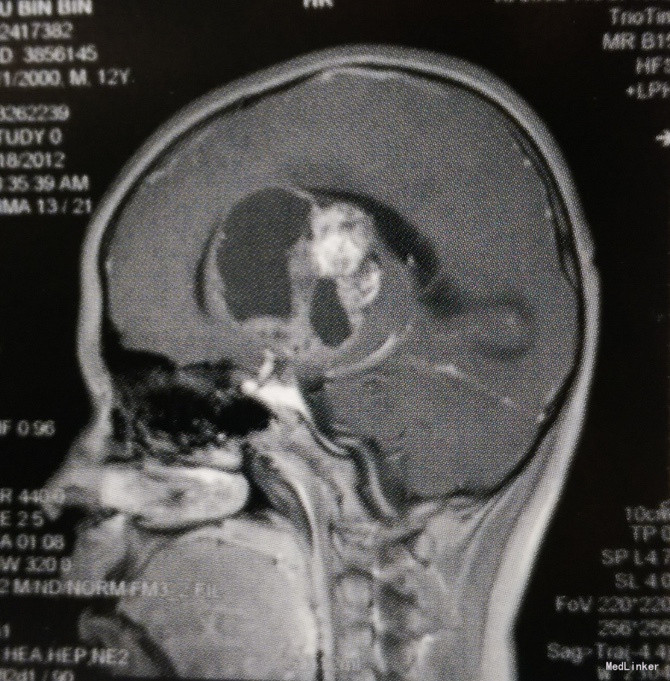

体格检查:意识呈昏睡状,查体不配合,双侧瞳孔等大等圆、对光反射迟钝,四肢肌力III级,肌张力轻度增高,右侧Babinski征阳性,颈抵抗阳性。 头颅MRI检查:左侧基底节区及丘脑占位性病变,呈囊实性混杂成分,边界欠清,实性成分呈明显不均匀强化,考虑生殖细胞瘤或胶质瘤可能性大;左侧侧脑室明显受压变形,中线向右侧移位;幕上梗阻性脑积水。